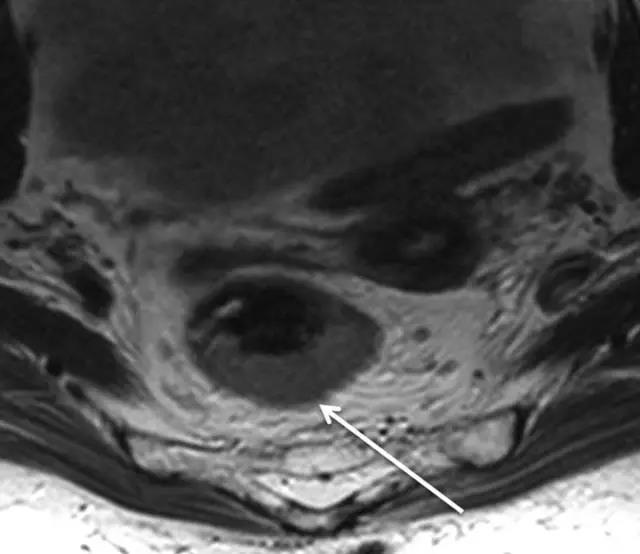

72 岁直肠癌男性,T2 加权轴位图显示 T1 肿瘤,紧邻肿瘤的粘膜下层消失而固有肌层完整。